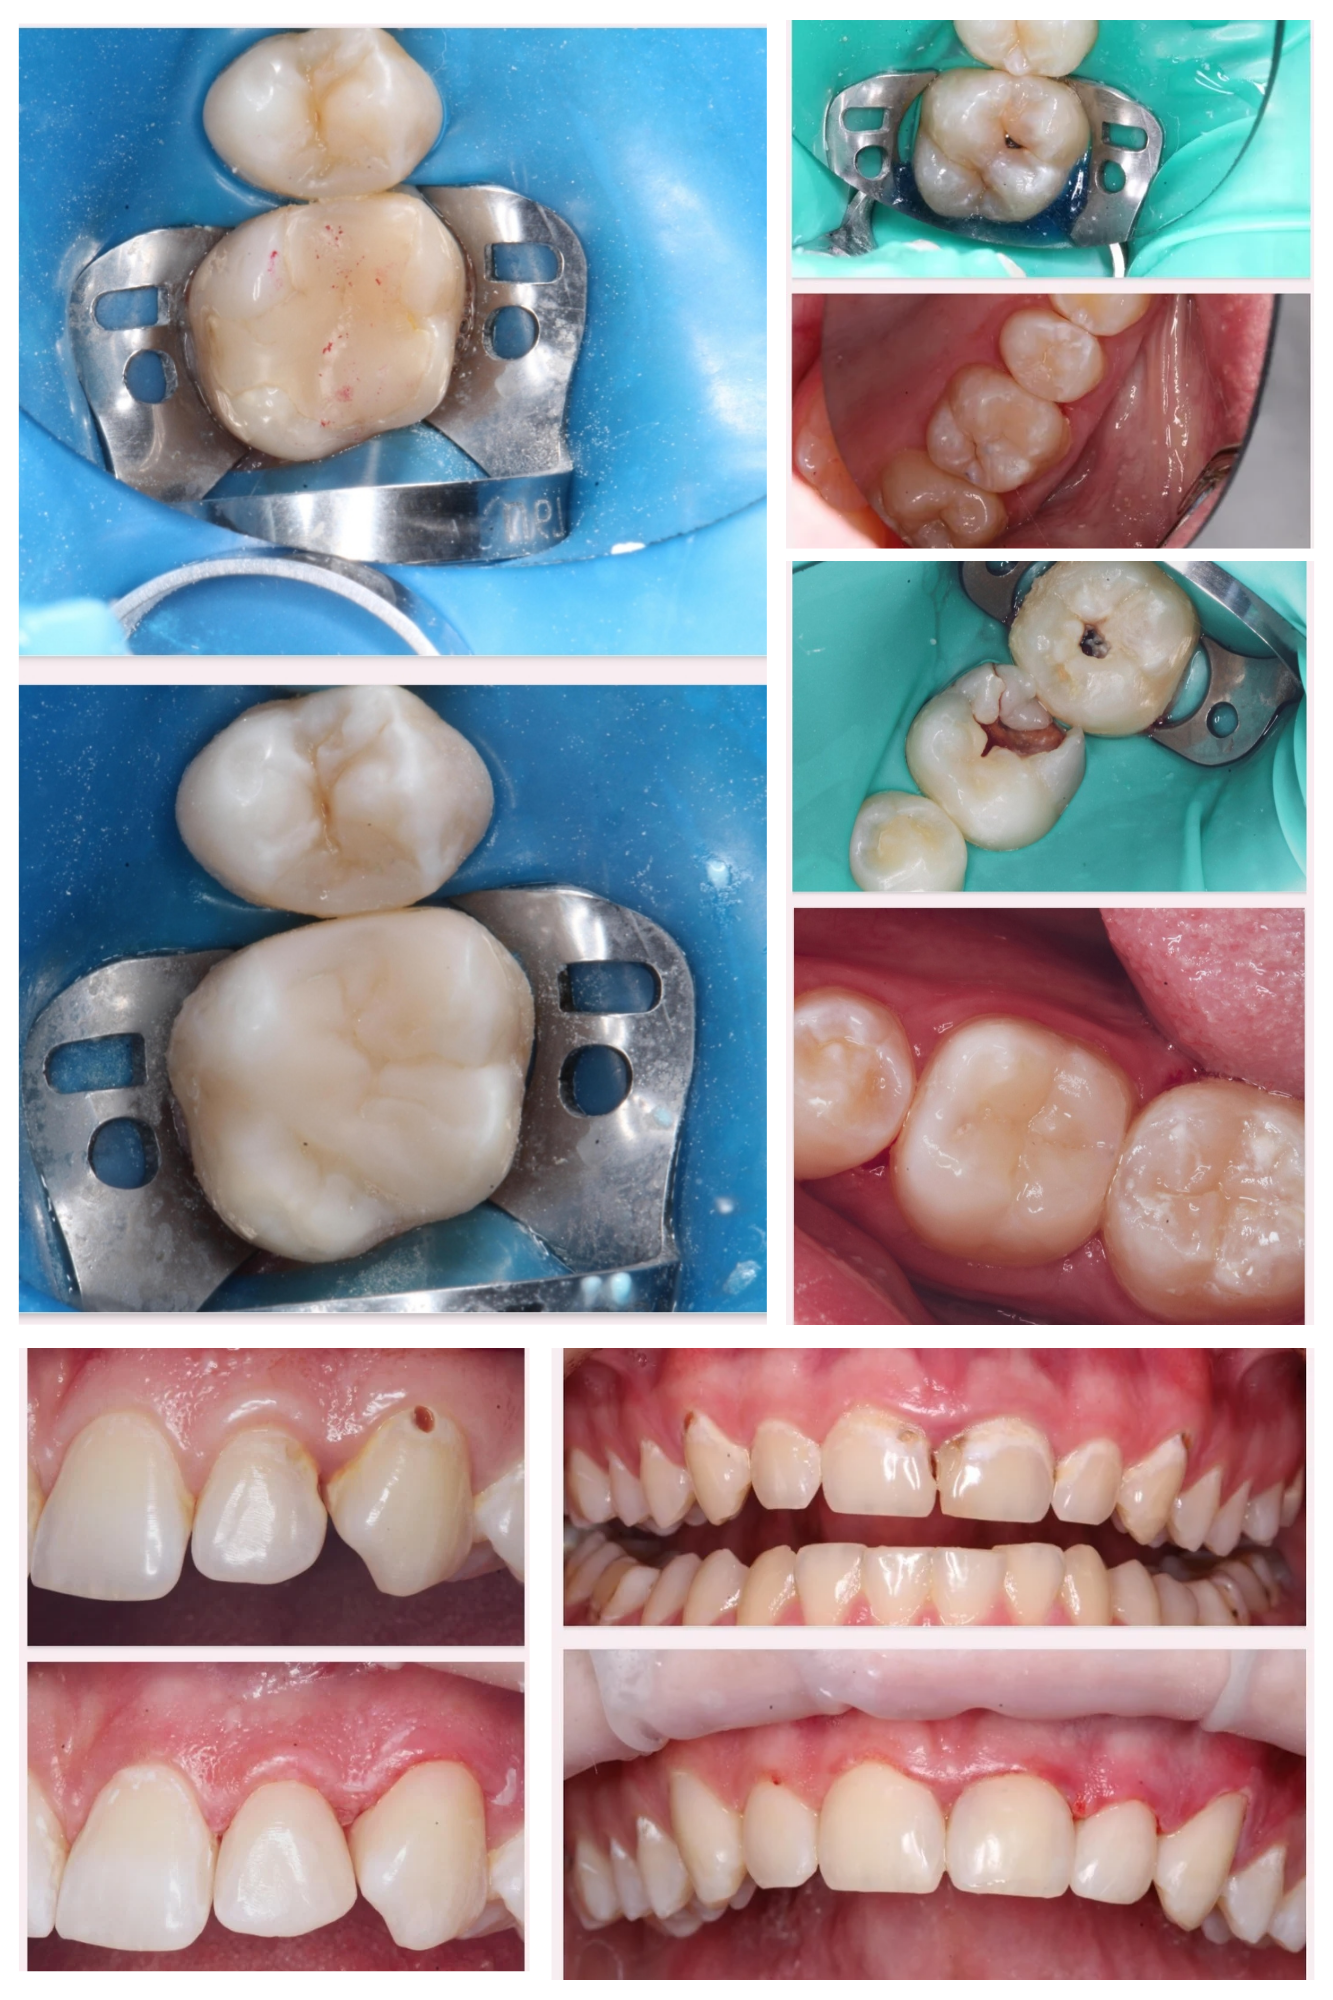

Примеры работ стоматолога-терапевта.

Клинический случай закончен отлично, а вот НЕСОБЛЮДЕНИЕ ГИГИЕНЫ во время ортодонтического лечения привело к изменению эмали зубов!

❗Будьте ответственны к своему здоровью! Соблюдайте гигиену полости рта!❗

✔Обновлённая улыбка

🦷

Дома с ORMCO. Марафон прямых эфиров👍

✔Во время длительного ортодонтического лечения гигиена затруднена из-за наличия во рту брекетов, дуг, резинок и тд. ✔ Если гигиена не поддерживается на должном уровне, на эмали зубов образуется начальный кариес в виде белых (желтоватых) пятен, который может превратиться в полости или “дырки” (на левой фотографии).✔ Обращаю Ваше внимание, что брекеты зубы не портят! Отсутствие гигиены портит зубы! ✔На правой фотографии современное решение этой проблемы – лечение кариеса без сверления, метод инфильтрации кариеса ICON.

✔Хочу показать жизнь без прикрас ✔Отсутствие должной гигиены во время лечения, которое привело к гингивиту (воспаление десен) и начальной стадии кариеса (меловидные пятна на эмали зубов) ☑Этим постом хочу призвать всех брекетоносцев собдюдать правила гигиены ‼Запомните❗Брекеты не портят зубы! ❗Портит зубы отсуствие тщательной регулярной чистки зубов❗ ✅Дайте своему врачу возможность и время сделать вашу улыбку идеальной